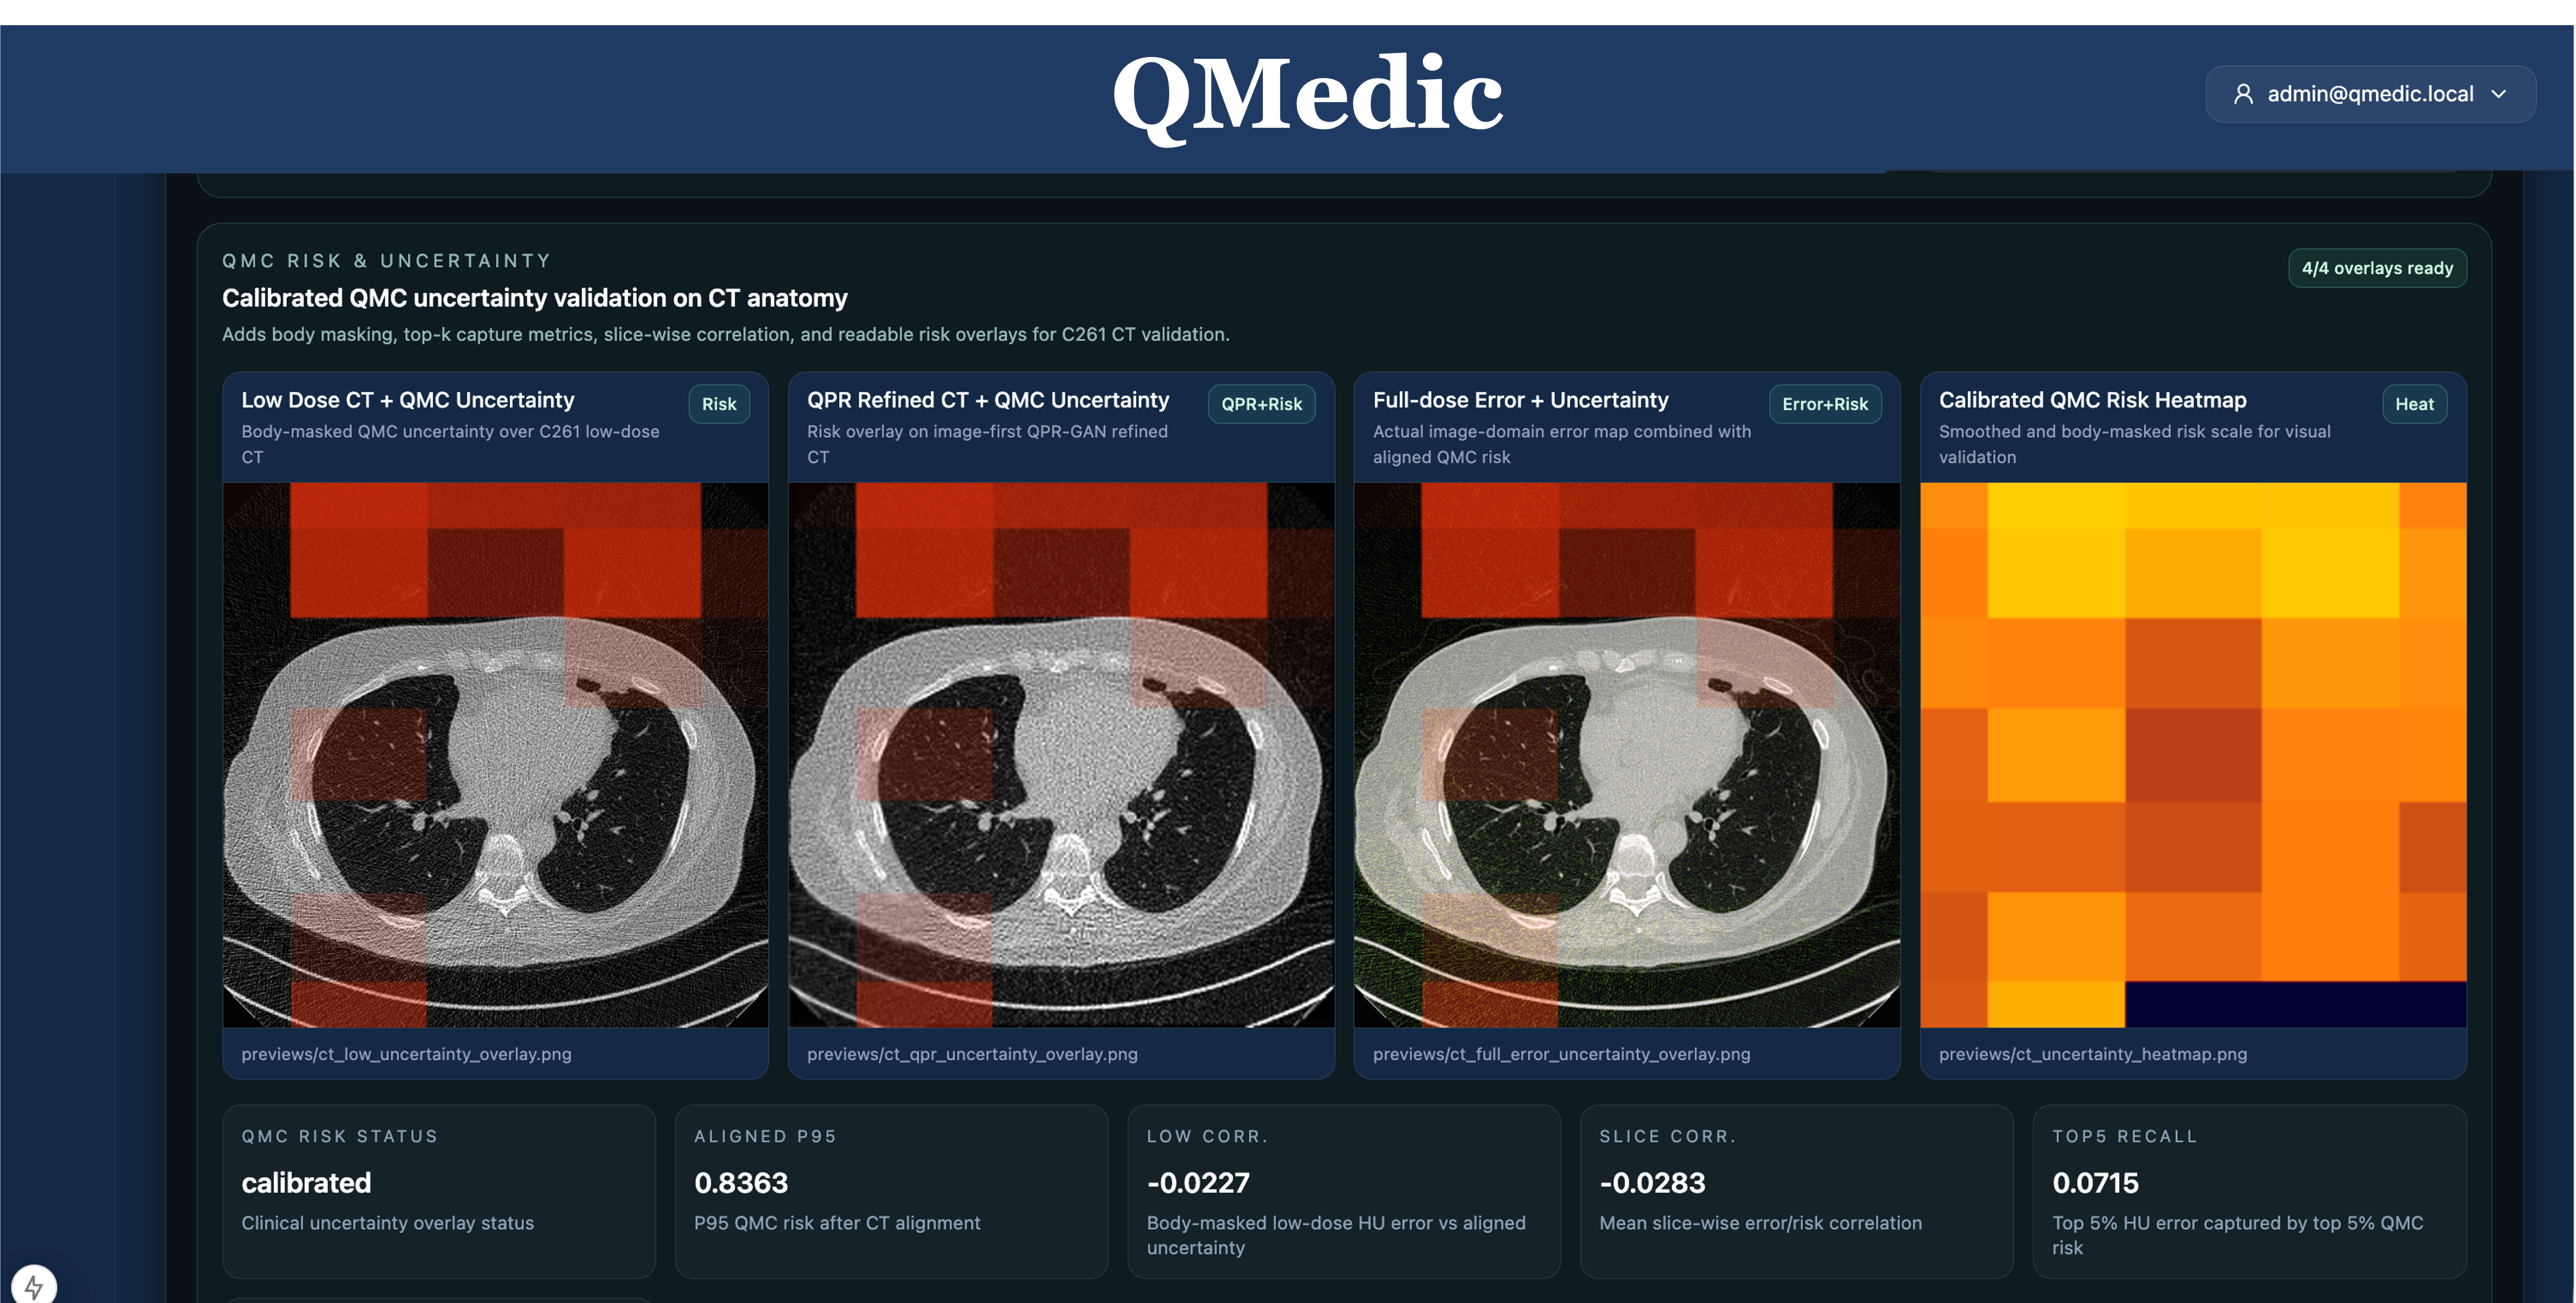

Lead commercial platform for CT/MRI-oriented reconstruction, QPR-assisted refinement, side-by-side comparison, and quality-governed imaging workflows.

The first commercial wedge is QMedic in CT and MRI reconstruction, refinement, comparison, and quality governance. The same platform can extend into digital twins, inverse problems, energy and wind-system optimization, and other HPC-intensive workflows where trust and traceability matter.

QMedic packages reconstruction, QPR-guided refinement, comparison, and quality governance for hospitals, research imaging teams, imaging software vendors, and medical AI partners.

Lead with QMedic in CT/MRI reconstruction, refinement, and quality-governed imaging workflows for research and hospital-adjacent buyers.

Public coverage of QMedic as SQK’s reliability-centered medical imaging platform for reconstruction, refinement, and quality-governed workflows.

Research publication supporting QMedic’s imaging credibility and reinforcing SQK’s trust-centered product positioning.